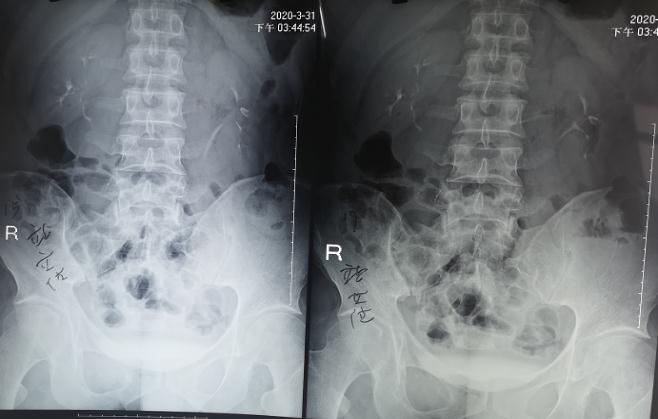

術前靜脈腎盂造影檢查: